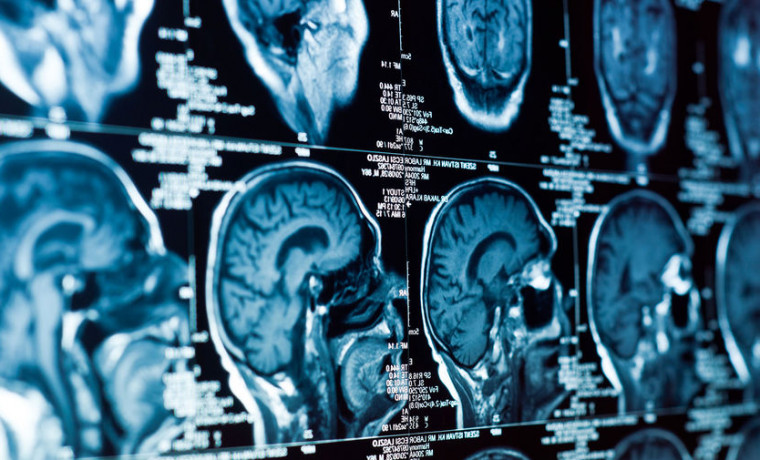

По словам иммунолога Михаила Костинова, нейроковид и длинный ковид теоретически могут быть вызваны омикрон-штаммом. При оценке состояния пациента нужно обращать внимание на возраст, наличие прививки и сопутствующие заболевания.

"Насчет нейроковида — как правило, все-таки речь идет о поражении отдельных органов. Чаще происходит ситуация, когда вирус влияет, например, отдельно на свертываемость крови, обоняние, ЦНС. Сейчас одним из симптомов являются боли в костях. Раньше были больше в мышцах. Также сейчас могут происходить воспалительные явления в костном мозге", — рассказал специалист.